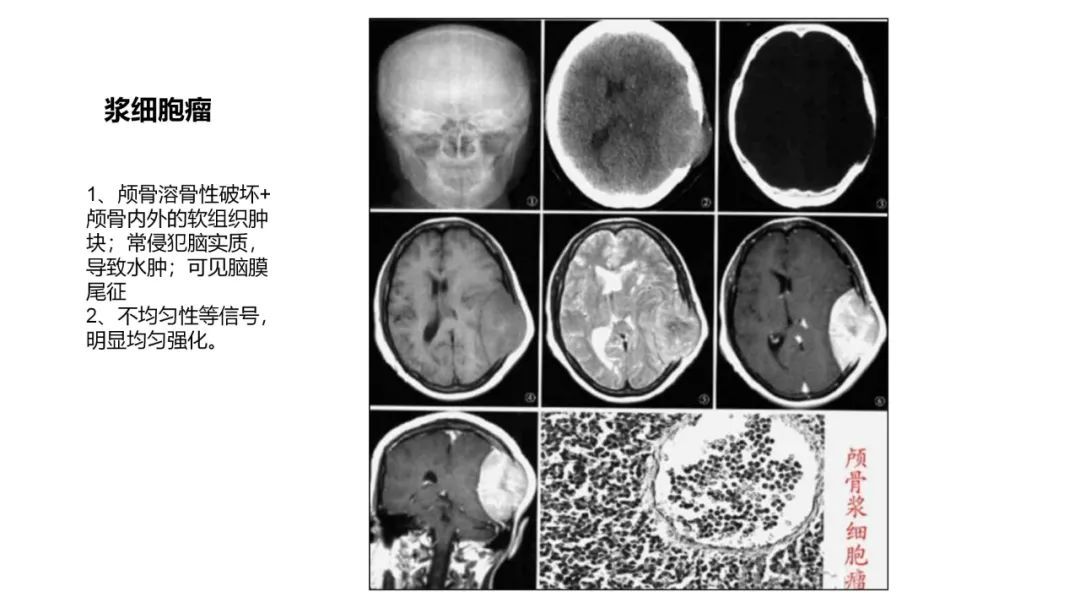

颅脑影像诊断基础知识讲座:颅骨病变